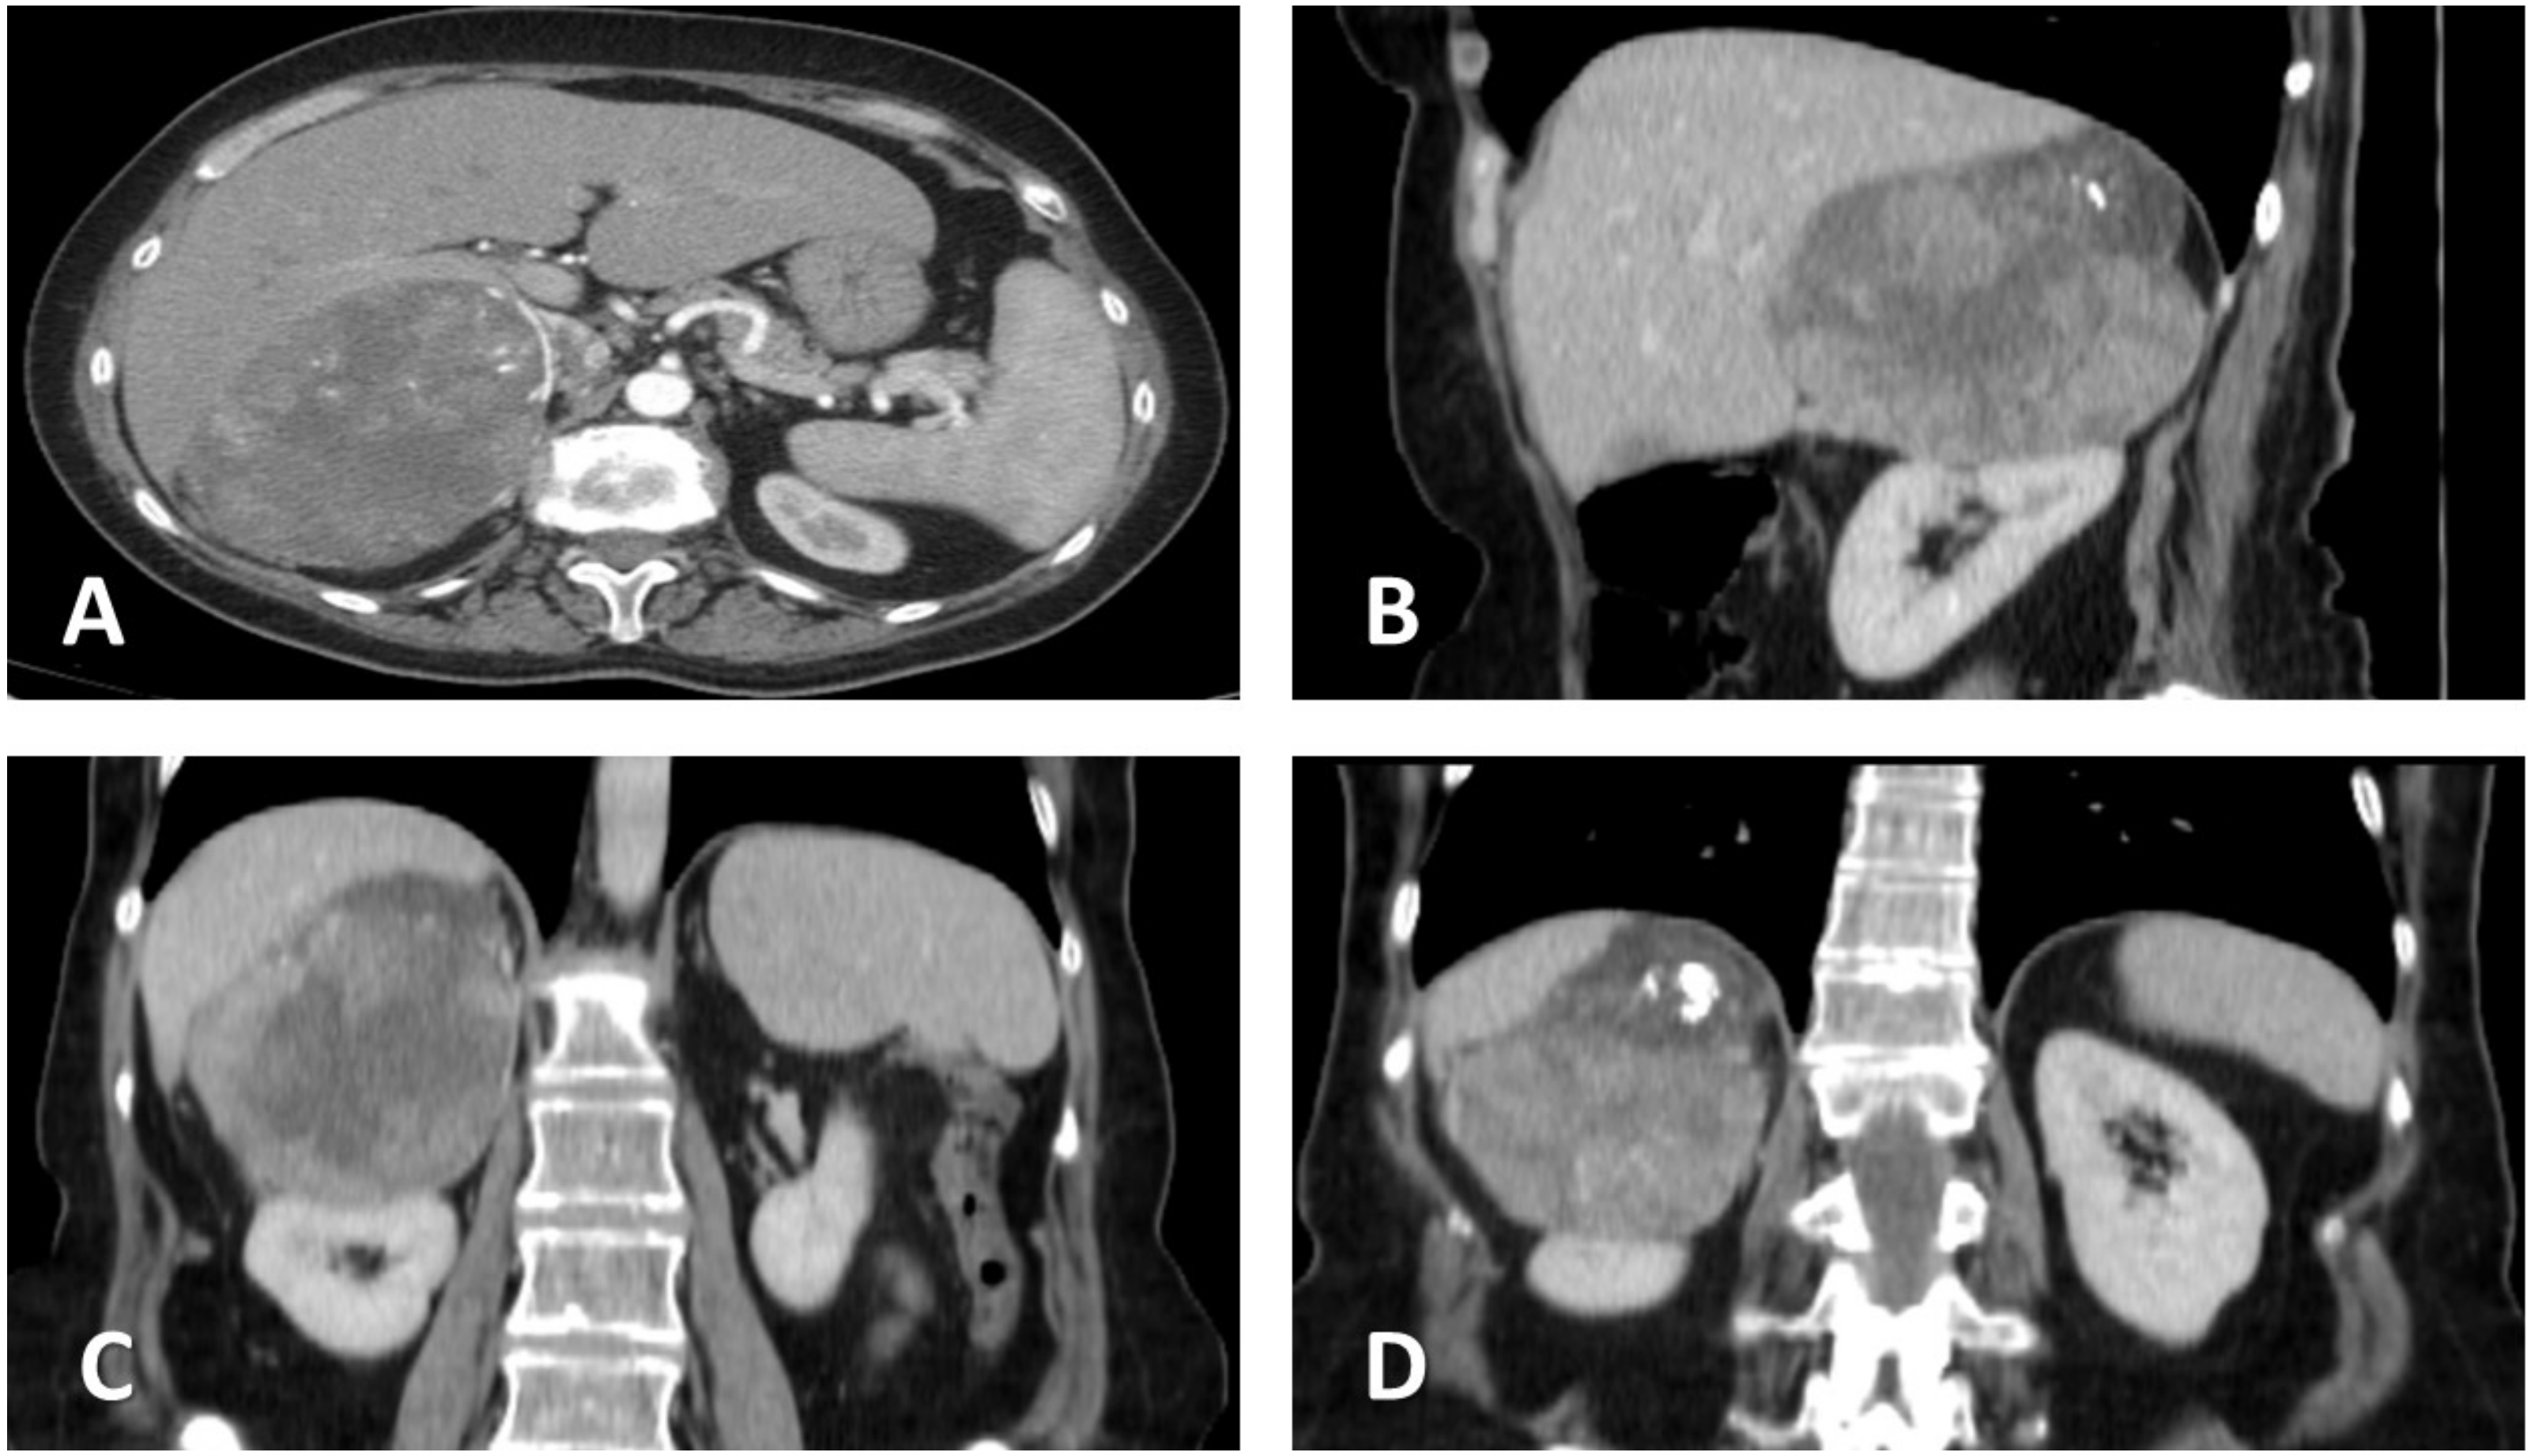

The patient underwent contrast-enhanced, thoraco-abdominal, and pelvic computer tomography (CECT-TAP), which confirmed a 149 × 106 mm tumoral mass with inhomogeneous structure and necrotic content, located in the right suprarenal region and extending into the upper renal pole, while compressing the right hepatic lobe and adhering at the level of the right diaphragmatic crus. The radiological characteristics indicated its adrenal origin, rather than an upper pole renal carcinoma. A similar mass of 82 × 63 mm was identified contralaterally, extending into the posterior gastric wall, spleen, pancreas, and upper left renal pole. No signs of lymph node involvement or distant metastases have been detected (Figure 1).

Figure 1.

Contrast-enhanced abdominal computer tomography. (A) Transversal plane, showing the close contact of the tumor with the right hepatic lobe. (B) Sagittal plane. (C) Coronal plane, showing possible hepatic and renal invasion, as well as central necrosis. (D) Coronal plane, illustrating upper tumoral calcification and suspected invasion of the diaphragm.